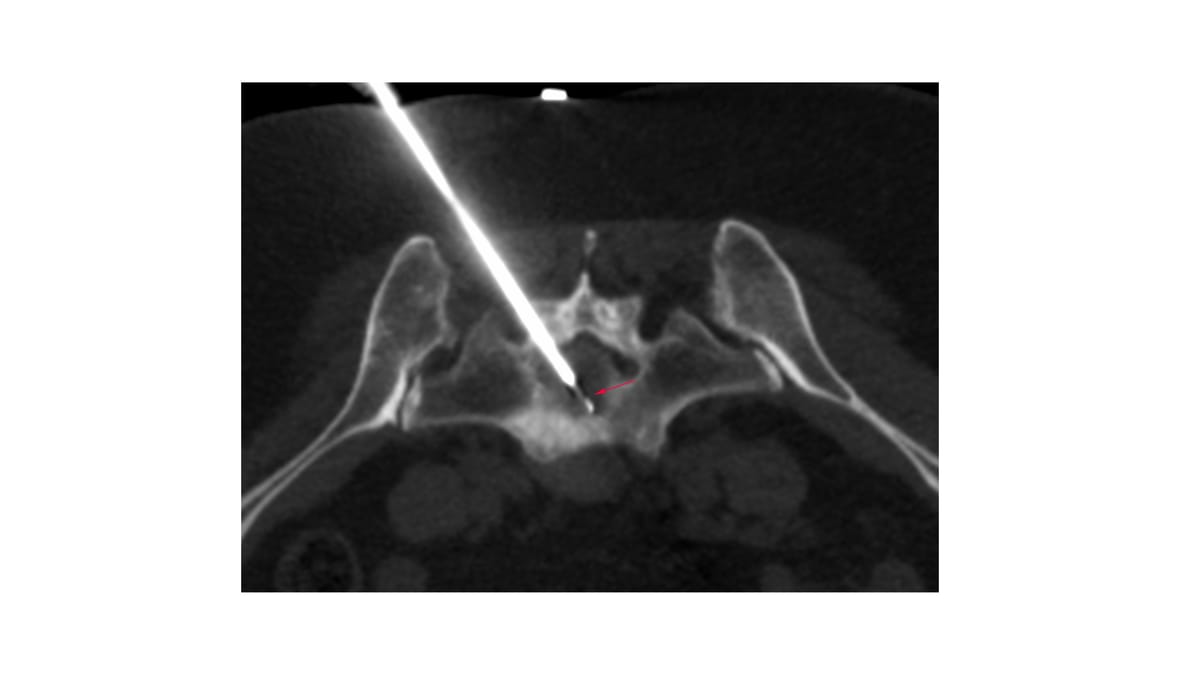

The patient was referred for a CT guided biopsy of the sacral lesion.